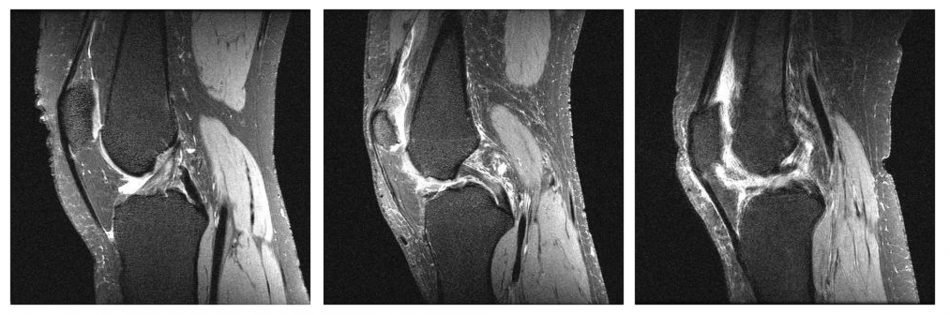

The medical image modality of magnetic resonance imaging (MRI) plays an increasingly important role in modern medicine, despite the high costs of these exams when compared to the decreasing costs of other imaging exams. Despite advances and investments in technologies, the attempt to take advantage of these studies in cost reduction is still modest in recent years.

This research proposal aims to study and evaluate the reconstruction of MRI images with subsampled data in the frequency space (K space) through artificial intelligence (AI), with reduction of the examination time and consequently the exam costs. This study compares the feasibility and efficiency in different percentages of the sample.

The raw data in K space was sampled in a controlled way to reconstruct the images, resulting in an image with sparse data reducing the number of image information. Then, the sparse data undergoes a reconstruction process through AI techniques such as Deep Learning (DL).

The proccess resultss was compared to the original image, analyzing the image efficiency through reconstructed quantitative measures. In this work, the division of the image into separate rows and columns was used and worked as single sequences.

These sequences were used as input to a neural network and reconstructed to form the original sequence, before subsampling. Finally, an algorithm was used to join these sequences and shapes to the new rows and columns of the reconstructed image.

The results of this process were compared with the original image, analyzing the image efficiency obtained through quantitative measures of the quality of the reconstructed images, in this case, the structural similarity index (SSIM) and the mean square error (mean square error) - MSE), for the different subsampling weights in the K space.

Therefore, with this study, it was possible to obtain a more effective method than the conventional method, reducing the time required for this process.